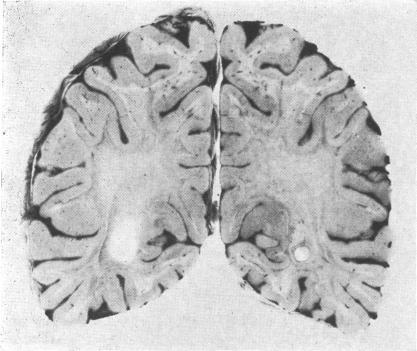

Adrenocortical atrophy and diffuse cerebral sclerosis.

A boy, diagnosed as having Addison's disease due to idiopathic atrophy of the adrenal glands at the age of 7 years, developed the first evidence of what was originally thought to be Schilder's disease' at 8 years and 10 months. He died at 9 years and 11 months. There was a very striking family history of autoimmune disorders on the mother's side. The clinical and pathological aspects of his case are outlined. Detailed studies of adrenal function during life showed a diminution in excretion of adrenal androgens and corticosteroids before therapy which was not evident from the 17-oxosteroid and 17-hydroxycorticosteroid assays in the resting state, though the initial diagnosis was based on the failure of ACTH to produce a rise in the 17-hydroxycorticosteroid excretion. No unusual or abnormal steroids were detected nor was there any disproportion between the androgen and corticosteroid excretion to suggest an adrenal enzyme deficiency. The biochemistry of the brain at necropsy revealed the changes expected in a demyelinating disorder, but the detection of abnormalities in the grey matter distinguished the condition from Schilder's disease' in which the biochemistry of the grey matter is normal. There are 12 fully documented reports of boys with adrenocortical atrophy and diffuse cerebral sclerosis, and it is thought that this rare entity is inherited as an X-linked recessive characteristic. The two likely theories of causation involve either an error of metabolism common to the adrenal cortex and the brain, or the possibility that both the adrenal and brain pathology are due to an autoimmune disorder.